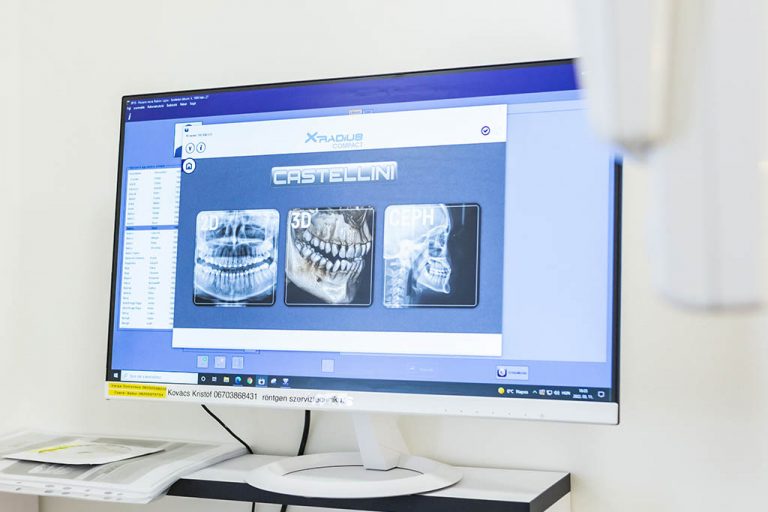

Szakorvosaink egyedülálló tapasztalatra tettek szert a fogászati problémák helyes és precíz feltérképezése terén, ami elengedhetetlen a megfelelő kezelési terv összeállításához és végrehajtásához. Munkájukat a legkorszerűbb 3D CBCT készülékek és egyéb fejlett diagnosztikai eszközök támogatják.

Röntgen diagnosztika

A teljes fogazatról készült panoráma röntgenfelvétel általános tájékozódást tesz lehetővé a páciens orális egészségügyi állapotáról. Az intraorális (szájon belüli) röntgen segítségével 1-2 fogról készítünk részletes, kétdimenziós felvételt, amivel még pontosabb diagnózis adható pl. gyökérkezeléseknél. Rendelőnkben ún. kefalometriás röntgenfelvételeket (teleröntgen) is készítünk, amelyek pl. a fogszabályozásban játszanak szerepet.